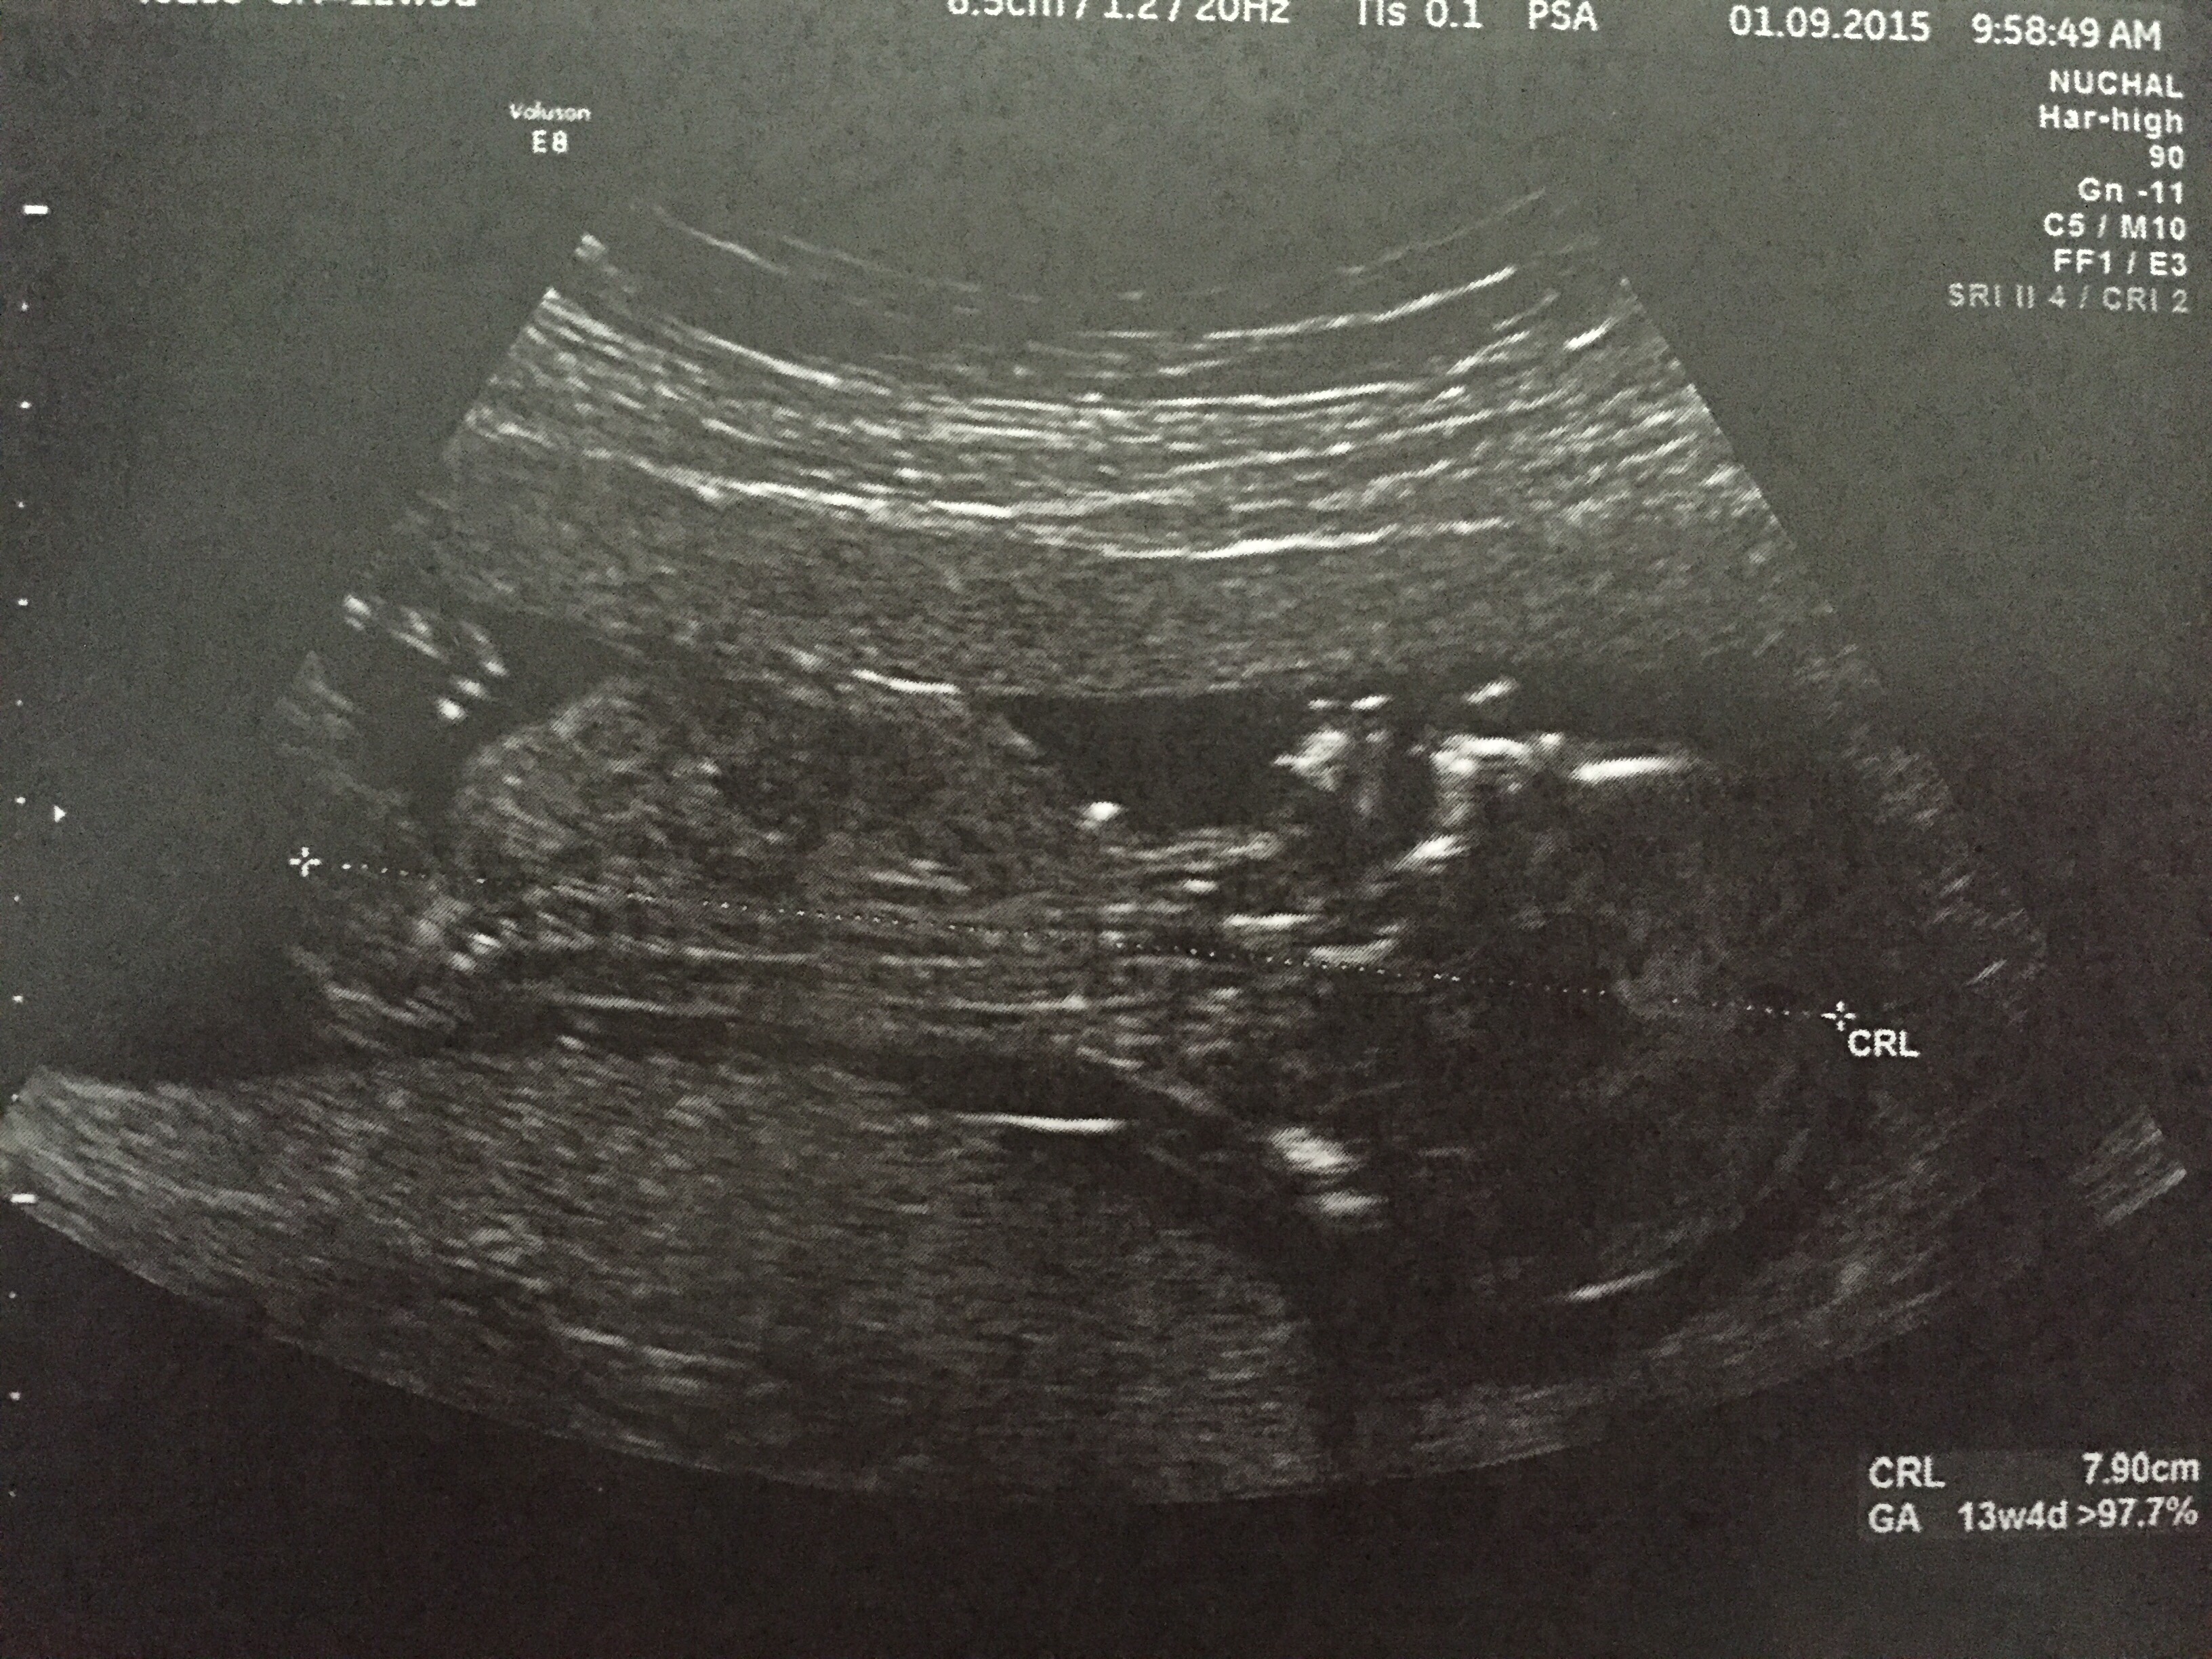

I'm thinking blue but how many weeks?

I was 13 weeks, 6 days for this scan

Pics are a little dark and are hiding their detail unfortunately but I am getting a general pink feeling :)

I think I'd expect to see a little more than I am if it were boy so going to lean girl

No real clues, sorry.